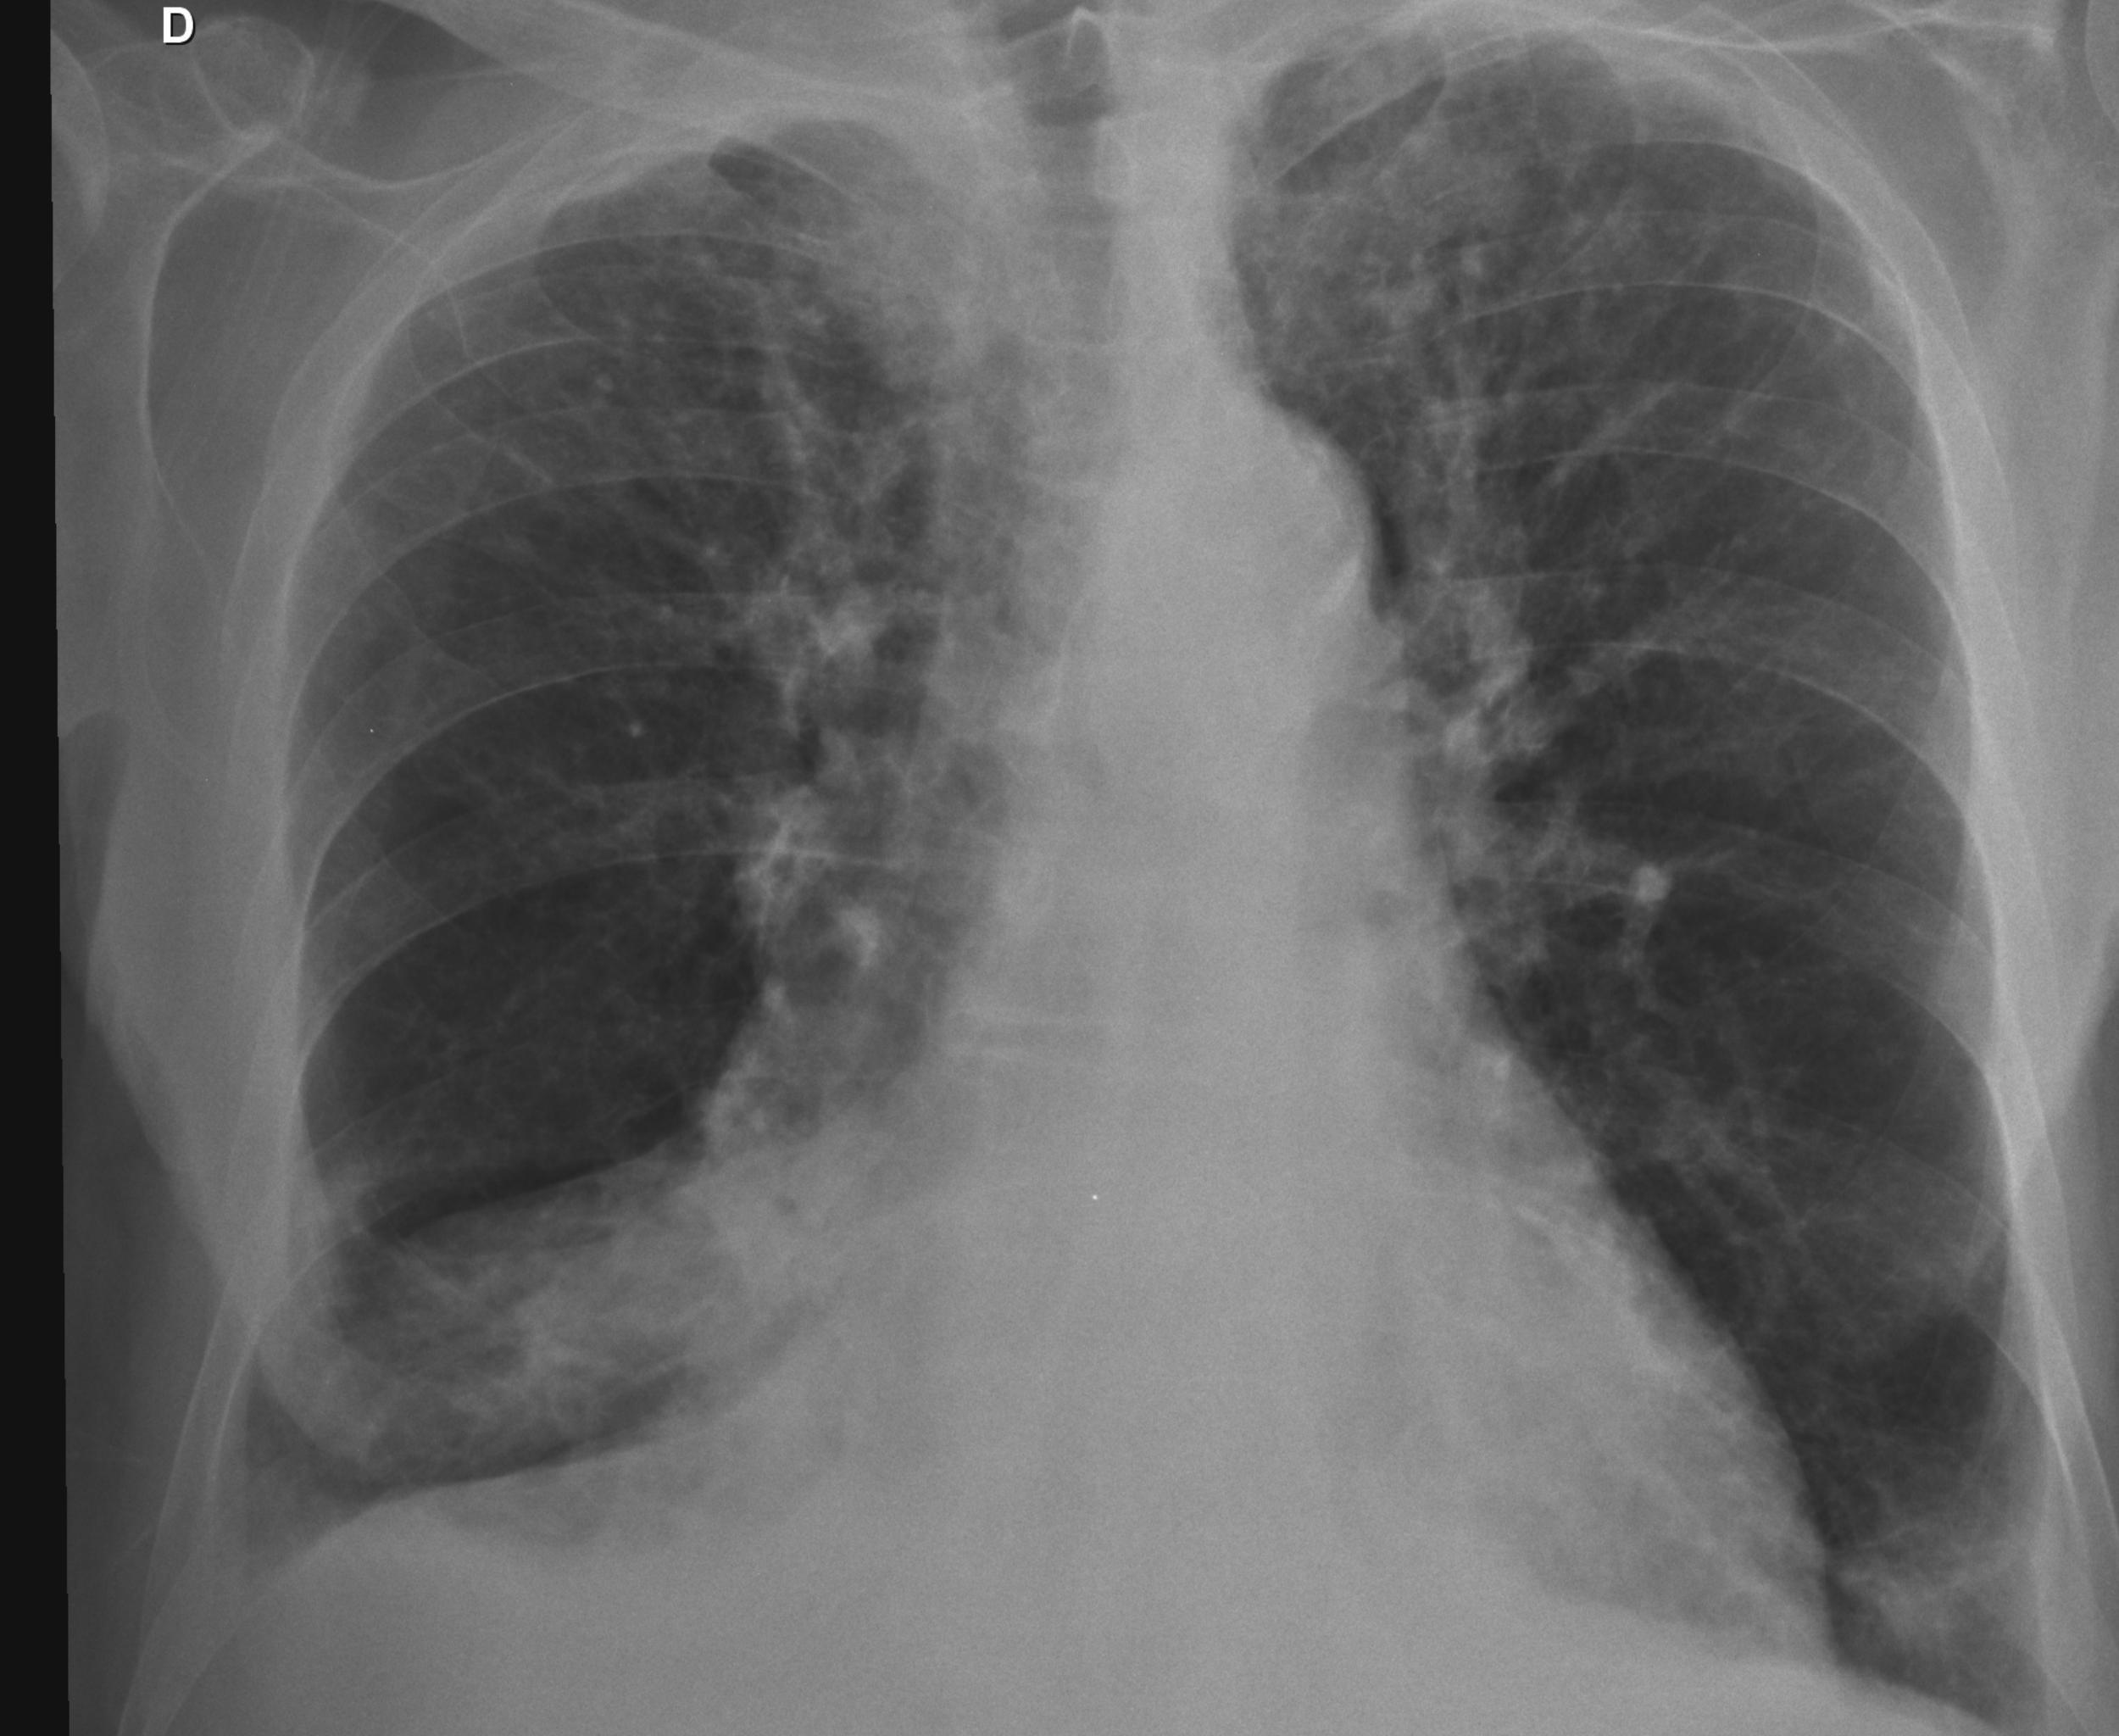

Caso relatado na Reunião de Discussão de Casos Clínicos do Hospital Universitário Prof. Polydoro Ernani de São Thiago, iniciada pelos Profs. Jorge Dias de Matos, Marisa Helena César Coral e Rosemeri Maurici da Silva, em julho de 2017. No dia 14 de junho de 2018, no auditório do HUPEST, realizou-se a apresentação e discussão do caso cujo registro é apresentado a seguir. Trata-se da discussão de onze casos em radiologia torácia, de forma interativa com a plateia, e assim ocorre também neste artigo.